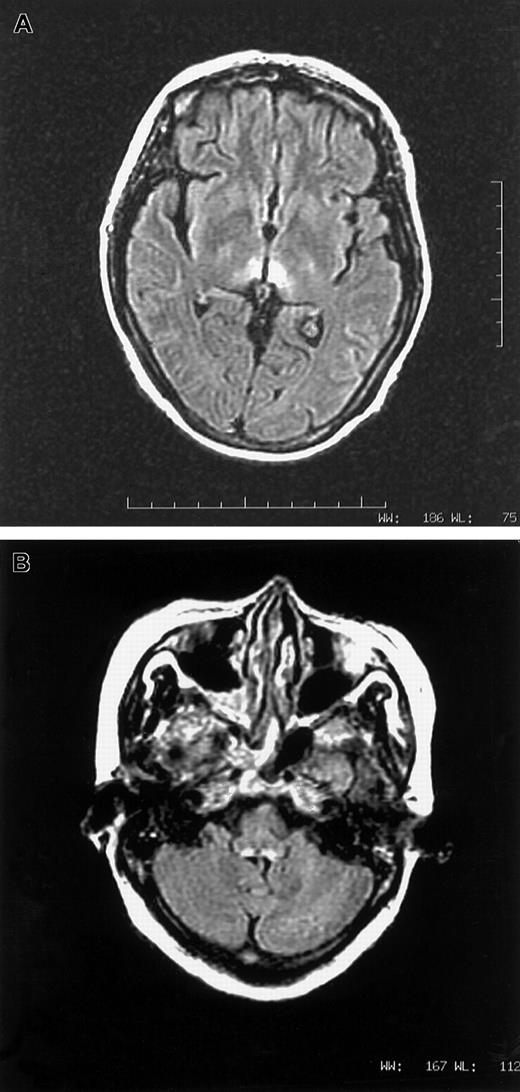

Fig. 1.

(A,B) MRI images in axial fluid attenuated inversion recovery sequence showing T2-weighted hyperintense lesions surrounding third ventricle (1A) and dorsal aspect of medulla (1B).

A vegetarian woman, aged 46, with relapsed APL, t(15:17), was given arsenic trioxide 10 mg/d for 28 days. Her first induction with all-trans retinoic acid and daunorubicin a year ago was uncomplicated. Medical history was unremarkable. In particular, there was no prior neurological disorder. Her diet was mainly refined rice and leafy vegetables, very sparse in meat and beans. Starting from day 17, she experienced nausea and vomiting. Pain and congestion were noted over the tongue, throat, and conjunctiva. On day 33, she complained of numbness over lower limbs. Confabulation was absent. On day 37, all 4 limbs were paralyzed and areflexic. Speech was inaudible and bulbar paralysis was noted. She sweated heavily and had a vesicular rash over her body. Cerebrospinal fluid showed white count, 1/μL; protein, 0.5 gm/L; and glucose, 6.7 mM. Studies for Venereal Disease Research Laboratory, bacteria, fungus, virus, and oligoclonal band were negative. Nerve conduction study detected generalized reduction of sensory action potential. Motor conduction was normal, while electromyogram showed active denervation. Drug review did not suggest a neurotoxic side effect from any supportive medication. With cranial magnetic resonance imaging (MRI), lesions consistent with Wernicke syndrome were seen over tectum, periaqueductal gray, and periventricular white matter of the third ventricle, both thalami, and the dorsal medulla (Figure1A,B). The low level of red cell (RBC) transketolase (24 μmol/min L; normal 45-90 μmol/min L), which increased by 32% after in vitro addition of thiamine pyrophosphate, confirmed thiamine deficiency. Parental thiamine 100 mg/d was given. The next day, power of the upper limbs dramatically improved and speech became audible. Over the next 5 days, upper limbs regained full power. As2O3 at 5 mg/d for 28 days as maintenance was given 5 weeks later, with oral thiamine. There was no deterioration in neurology. Lower limb power continuously improved. RBC transketolase during arsenic maintenance was normal, and MRI scan demonstrated complete resolution of all previous abnormalities.